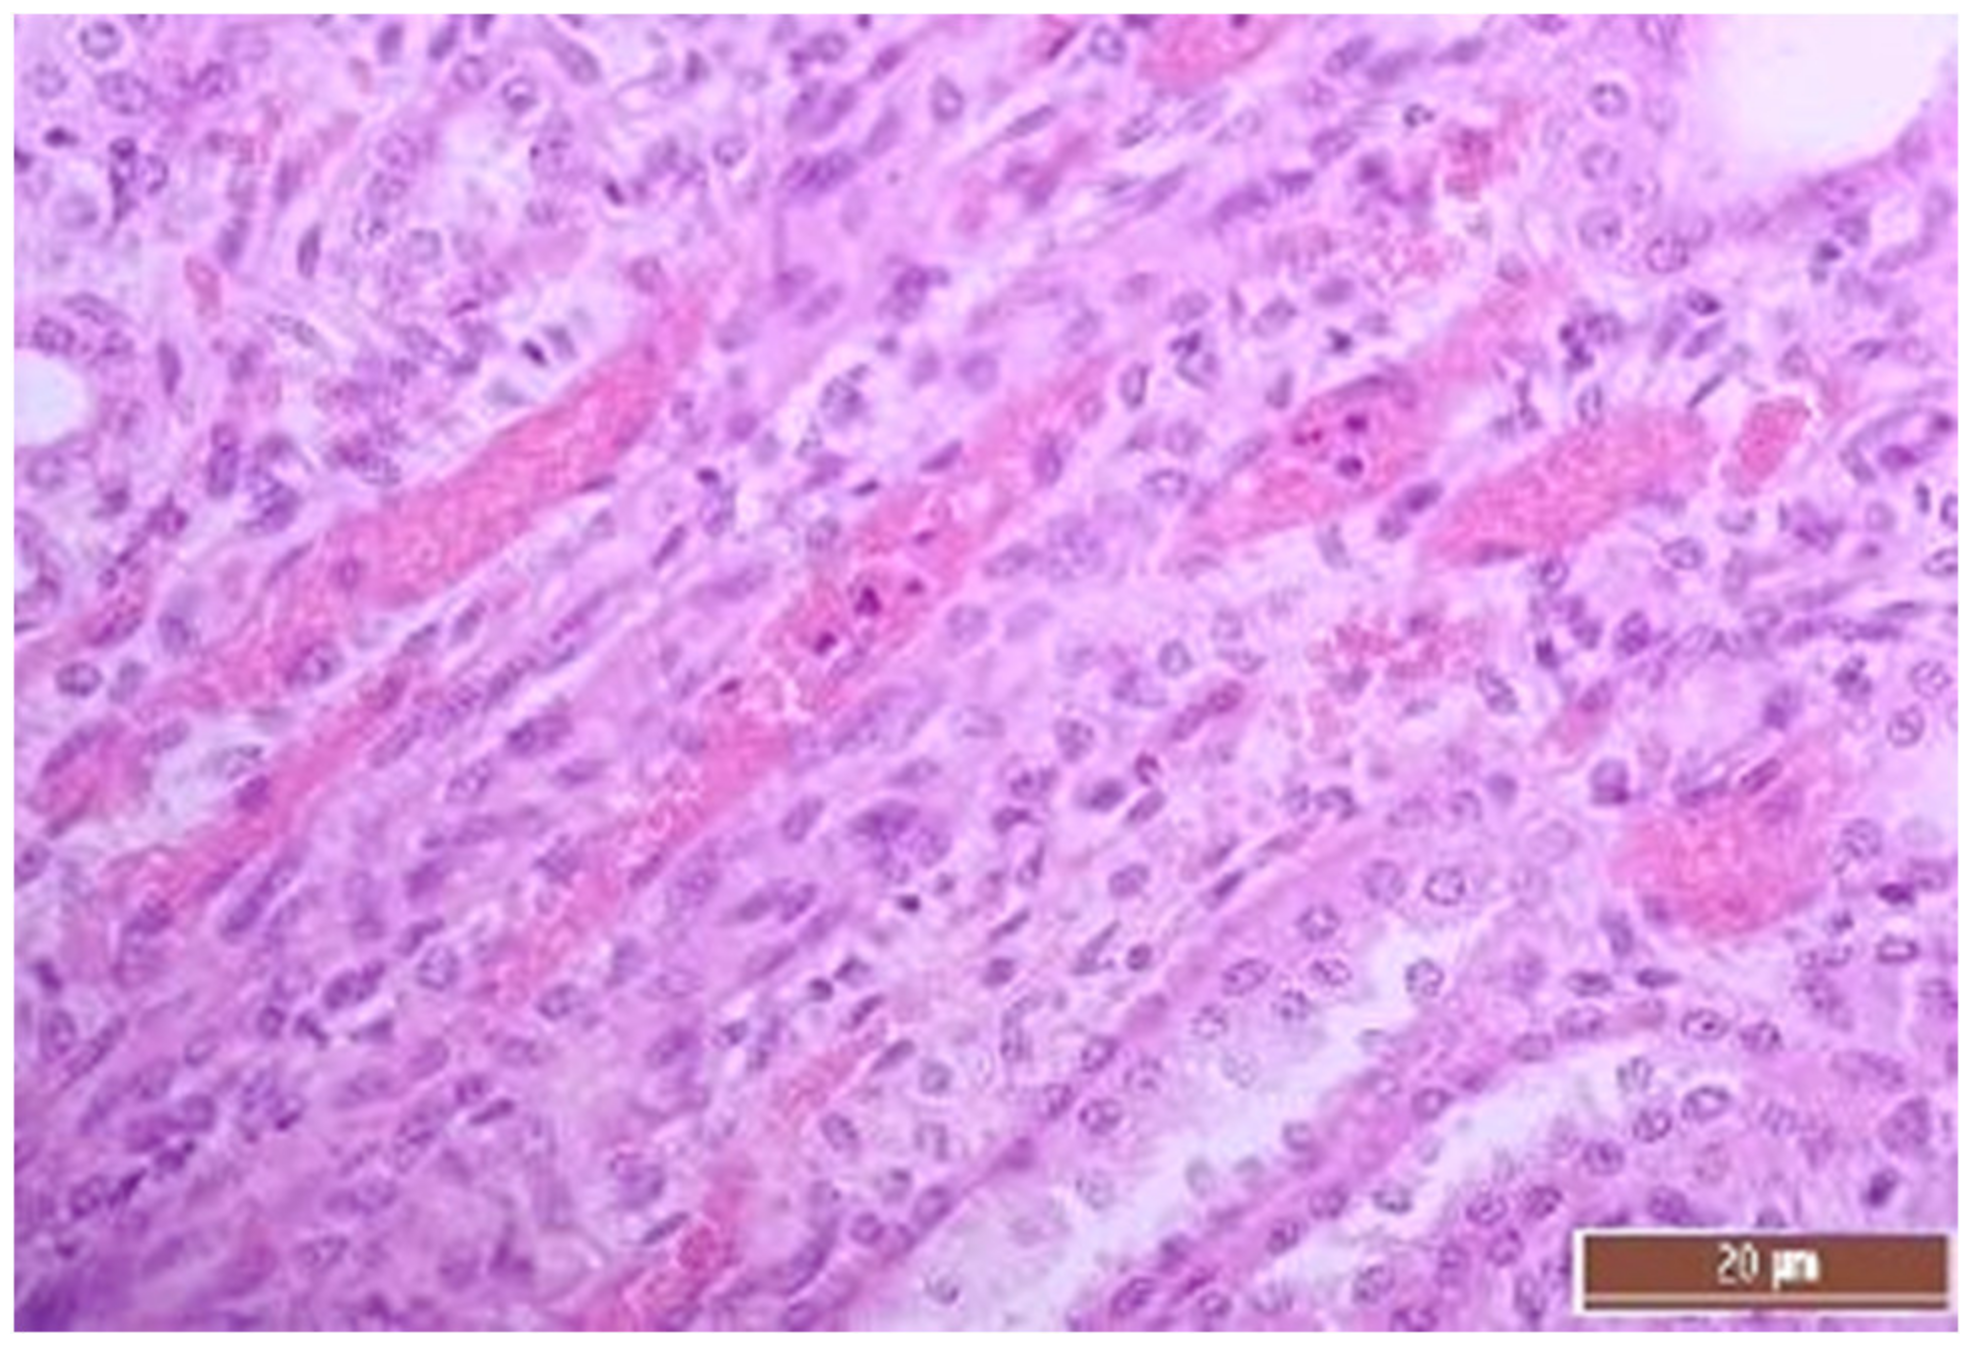

2.5. Pathomorphology

3.2. Pathology of the Liver

3.4. Pathology of Kidneys